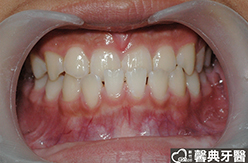

患者︰黃小弟弟,十三歲,學生。

主訴︰戽斗,想做矯正。

治療計劃︰上顎前牙排齊後彈出,下顎前牙排齊後後縮,重建正常咬合關係。